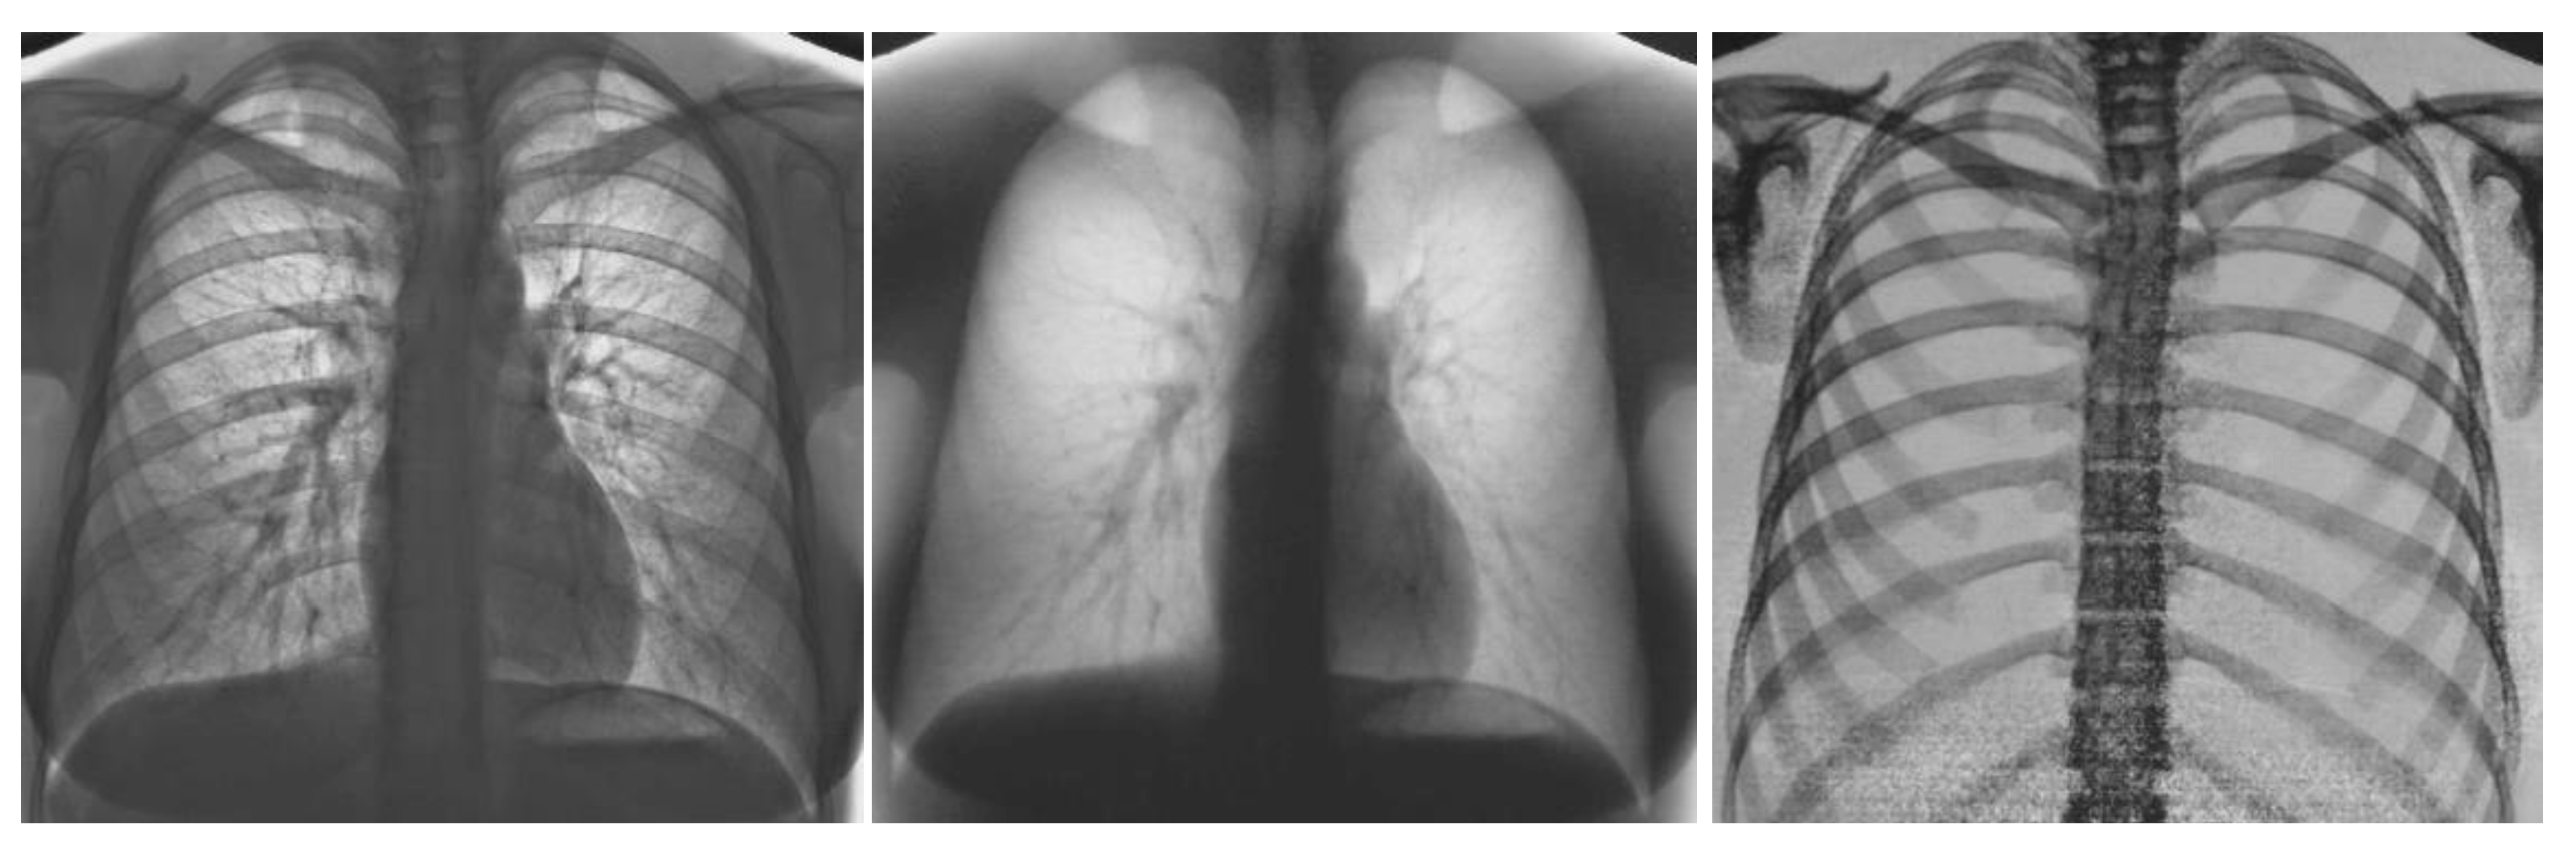

The application of CAD and radiomics to dual-energy X-ray imaging has not been adequately studied. Dual-energy chest radiography and more recently dual-energy or spectral CT have become commercially available and are routinely employed at many large medical centers. Advances in spectral CT are anticipated with the recent commercial introduction of photon counting CT. As illustrated in Figure 6 and Figure 7 dual energy chest radiography permits one to obtain a conventional digital chest radiographic image as well as additional subtraction images with the bones removed (soft tissue image) and with the soft tissue structures removed (bone image). With this capability, the radiologists’ ability to detect subtle pulmonary nodules improved as well as their ability to discriminate between benign and malignant lesions [124,125]. It is anticipated that spectral imaging will also improve the power of CAD and Radiomics when applied to three or more distinctly different images of the same anatomical structures rather than to a single image. Dual-energy or spectral imaging compared to conventional single-energy X-ray imaging also provides reliable quantitative information that could be used to reduce false positives. It is likely that Radiomics will also benefit from the accurate and reproducible quantitative input that spectral x-ray imaging provides.

Figure 6.

Images obtained on a prototype dual energy digital chest radiographic unit at the University of Alabama Birmingham circa 1985 with a single exposure: the conventional digital image was obtained by adding the low and high energy images (left); soft tissue image (center) and bone image (right) [124,125].

Figure 7.

Images obtained on a prototype dual energy digital chest radiographic unit at the University of Alabama Birmingham circa 1985 with a single exposure of a patient with lesions present in both sides of the lung in the conventional digital image (left); Soft tissue (center) and bone (right) images of the patient. The nodule in the lung left side is calcified and benign. The nodule on right side is present in the soft tissue image and not in the bone image, was not calcified and was cancer [124,125].